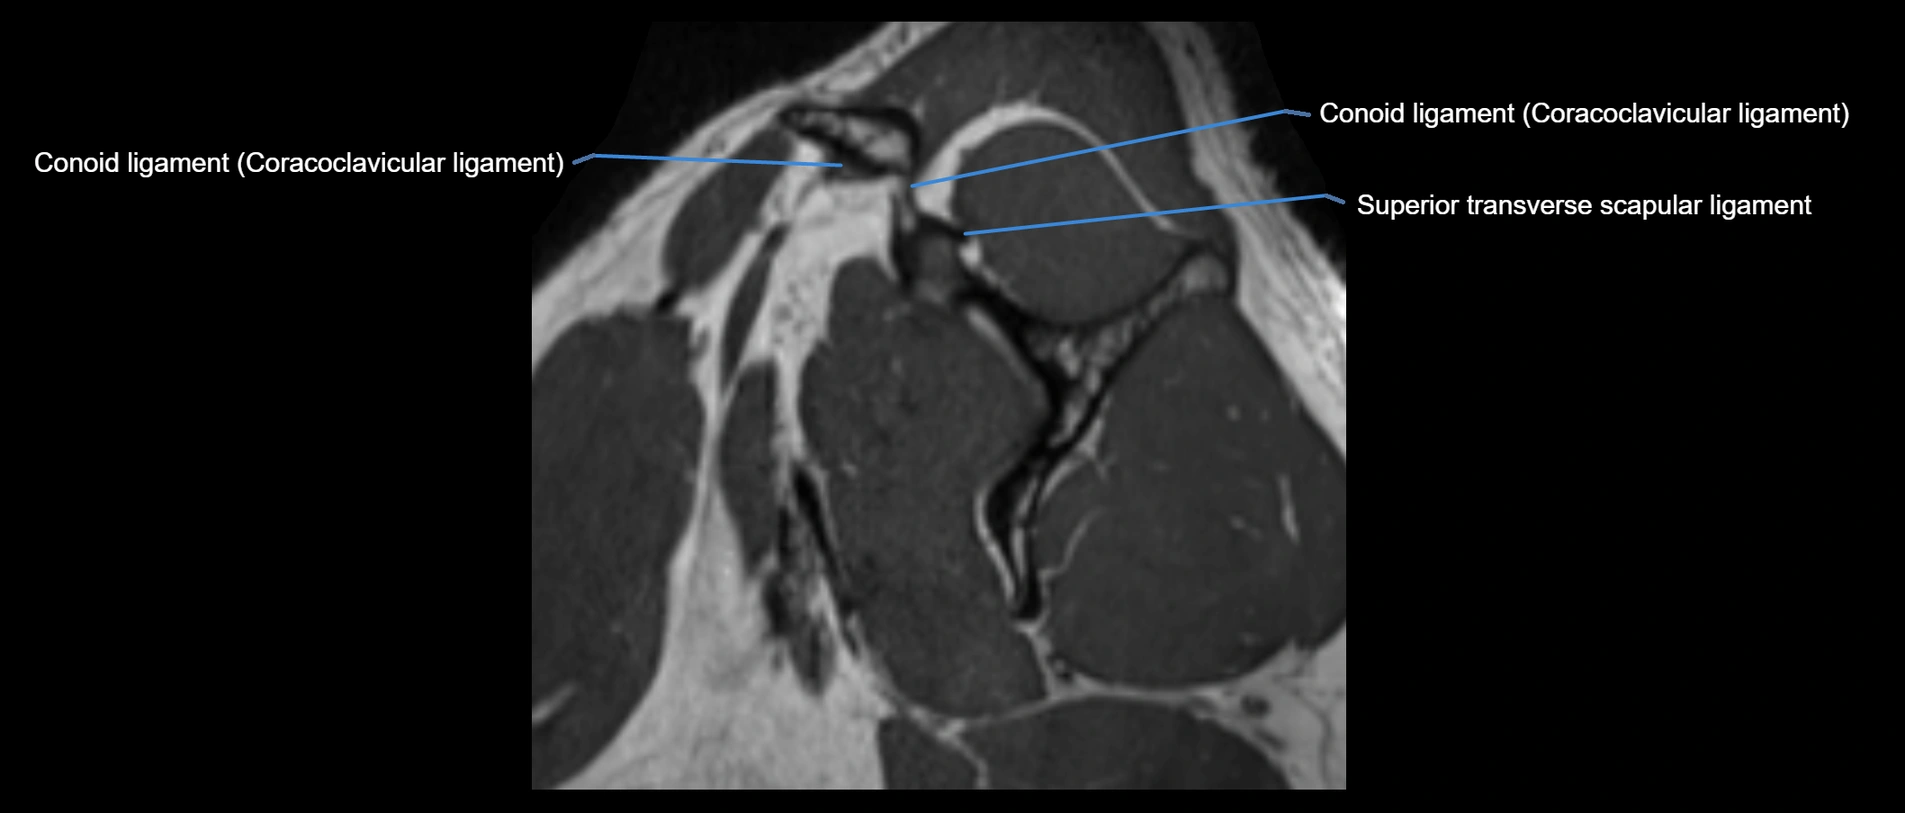

CT image

image

CT Appearance

Non-Contrast CT:

• Ligament: Not directly visualized due to small size and low density.

• Bony landmarks: Lateral clavicle and acromion clearly seen; cortical margins well defined.

• Pathology: Detects fractures, joint subluxation, osteophytes, and degenerative changes.

• Alignment assessment: Evaluates AC joint spacing and clavicular displacement.

Post-Contrast CT (standard):

• Ligament itself: Non-enhancing fibrous band.

• Inflamed capsule or soft tissue: May show enhancement.

• Useful for: Evaluating post-traumatic deformities, ossified ligaments, and chronic AC joint arthropathy.